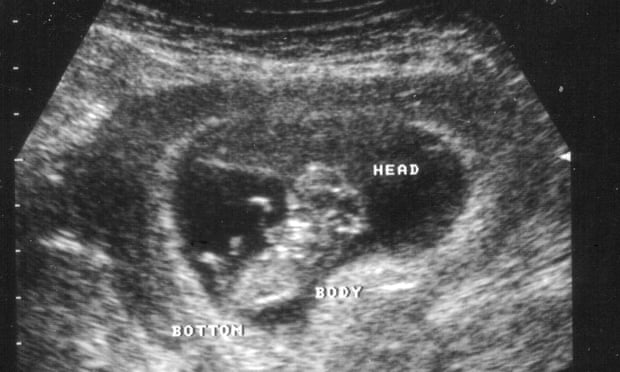

Improved technology has made testing for foetal abnormalities easier and more accurate, but inconsistent state legislation means women do not have equal access to abortion should they choose to terminate their pregnancy as a result, an editorial published in the Medical Journal of Australia on Monday says.

But despite Medicare-funded diagnosis of foetal abnormality now routinely being offered to pregnant women – with the implication that abortion may be an option if detected – abortion laws in Queensland and New South Wales do not refer to foetal abnormality.